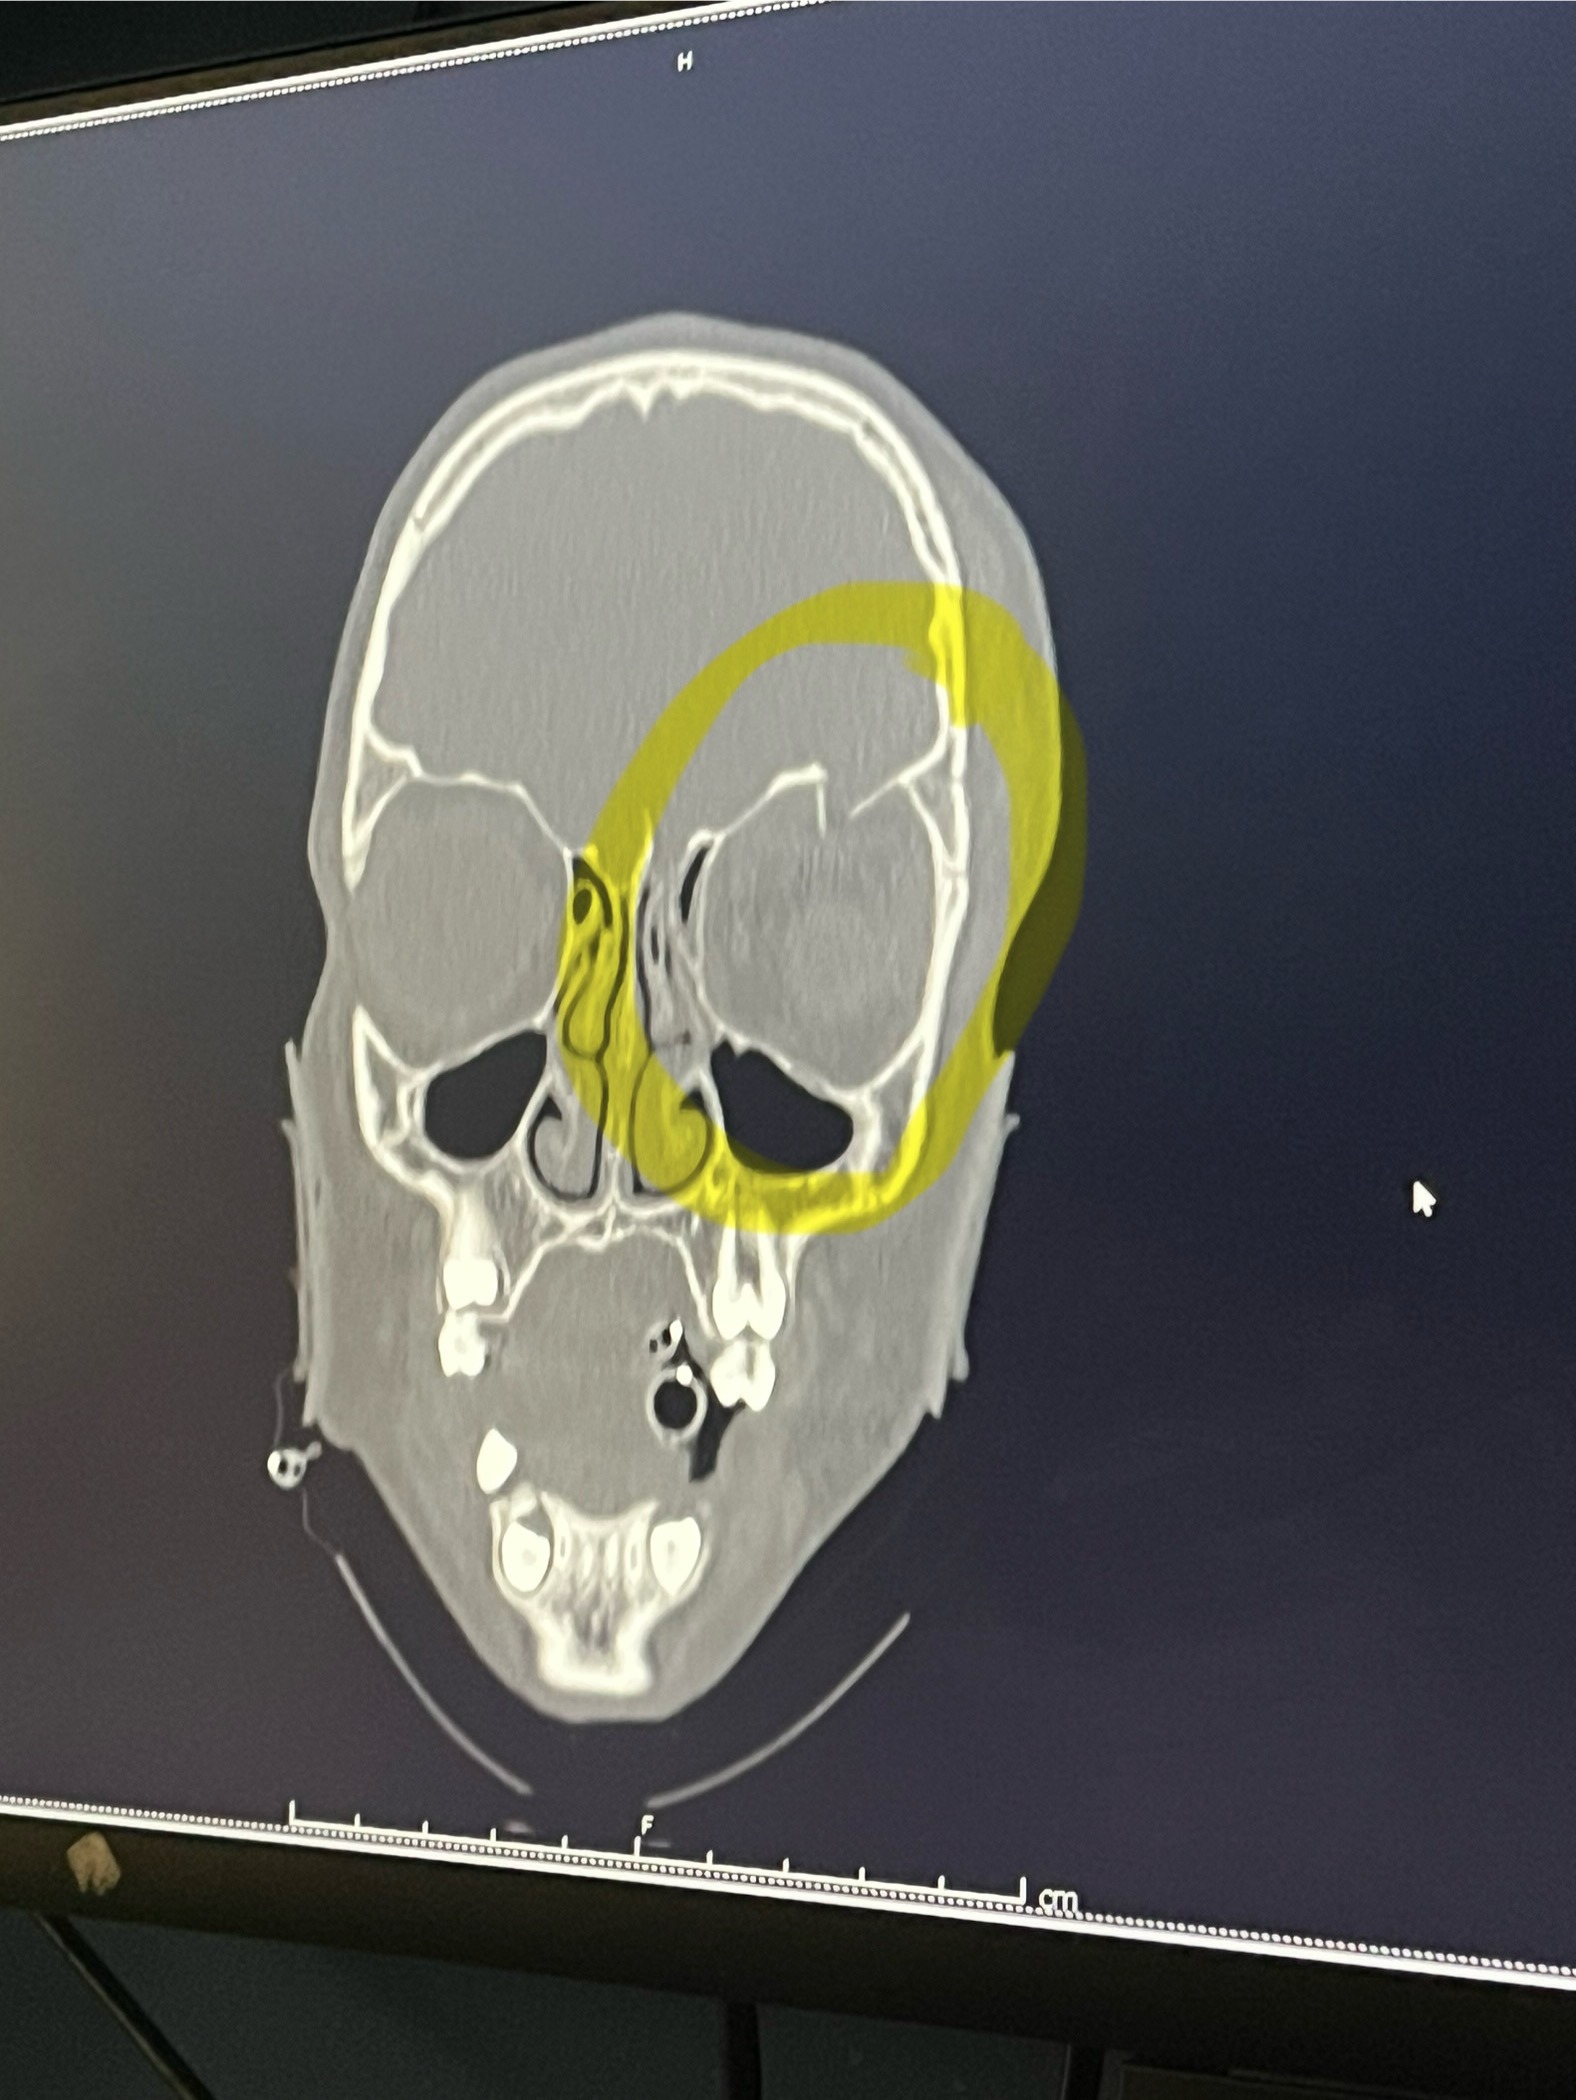

Doctors discovered that Sophia had suffered a large hematoma and swelling in her brain. The surgery had gone well and stopped the bleeding, and once the swelling went down, doctors realized she sustained a fracture to her skull above her eye, resulting in her eye socket needing reconstruction surgery in the following weeks.